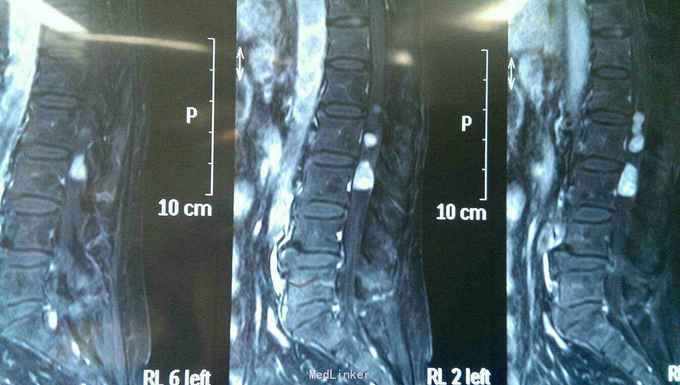

神志清楚,语言流利。颅神经检查未见异常。右侧臀部一下浅深感觉减退,肌力四级。生理反射存在,病理反射未引出。括约肌功能正常。核磁共振提示腰1--3椎管内多发病变,明显强化。

入院诊断椎管内多发占位病变,神经纤维瘤。完善术前准备后行后正中入路神经纤维瘤切除术。术中见马尾神经生长多个肿瘤,与其余神经无粘连,完整切除肿瘤。

术后患者无新增神经功能障碍,感觉麻木略有好转。多发神经纤维瘤在椎管内比较少见,术前定位关键,由于马尾神经控制括约肌功能,术中操作一定轻柔。